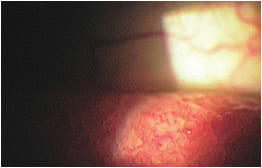

Classic giant papillary conjunctivitis.

PHOTO COURTESY: Derek Van Veen, O.D., M.S.